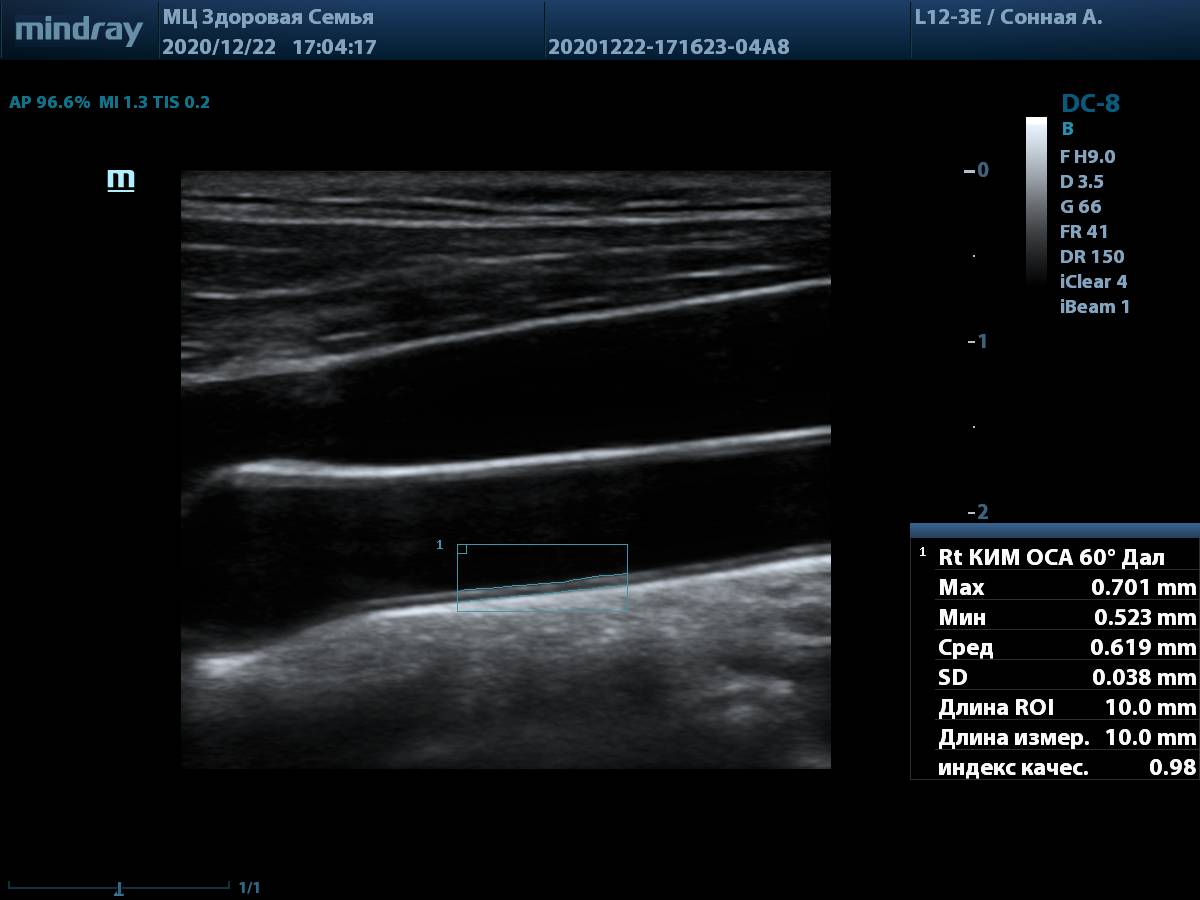

8. Общая сонная артерия (L12-3E) с использованием системы автоматического измерения комплекса интима-медиа, согласно международным стандартам.